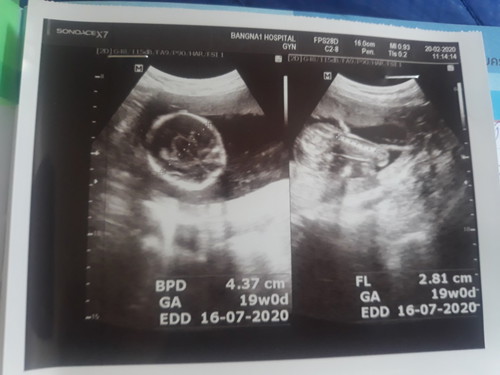

แบบนี้ชายหรือหญิงคะเพื่อนๆพอดูออกมั้ยคะ19W+

หมอบอกแค่ว่าร่างกายครบสมบูรณ์แล้วค่ะ

เเง น้องหนีบค่ะ ไม่ให้ดูเลย😂